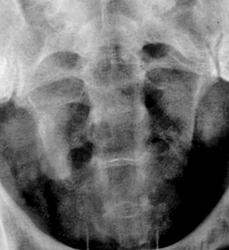

Признавайтесь, куда делась средняя треть правого мочеточника? Ее как-будто ножом отрезали под линейку, а ниже-сплошное безобразие! "ЧТО" может как обезобразить орган-банальная МКБ с частичной обтурацией просвета или опухоль? А в пузыре тоже камни?

Фи, доктор, это не латынь? Хотя можно выразиться и покрепче. Но в/в не дала ответов-где и что это?

А деформация мочевого пузыря никого не смущает?

Отчего же не смущает?))) смущает...она и есть первопричиной образования ТАКОГО камня в мочеточнике, теперь об этом можно сказать с уверенностью, ее генез - выраженое увеличение размеров простаты.

С простатой при отсутствии УЗИ достаточно пальцевого осмотра хирургом до экскреторного исследования. Если простата не увеличена пальпаторно, то получив такую картинку мочевого пузыря на первых минутах после введения контраста, я бы сделал косые снимки мочевого пузыря (заодно и тень в н/3 правого мочеточника покрутить).